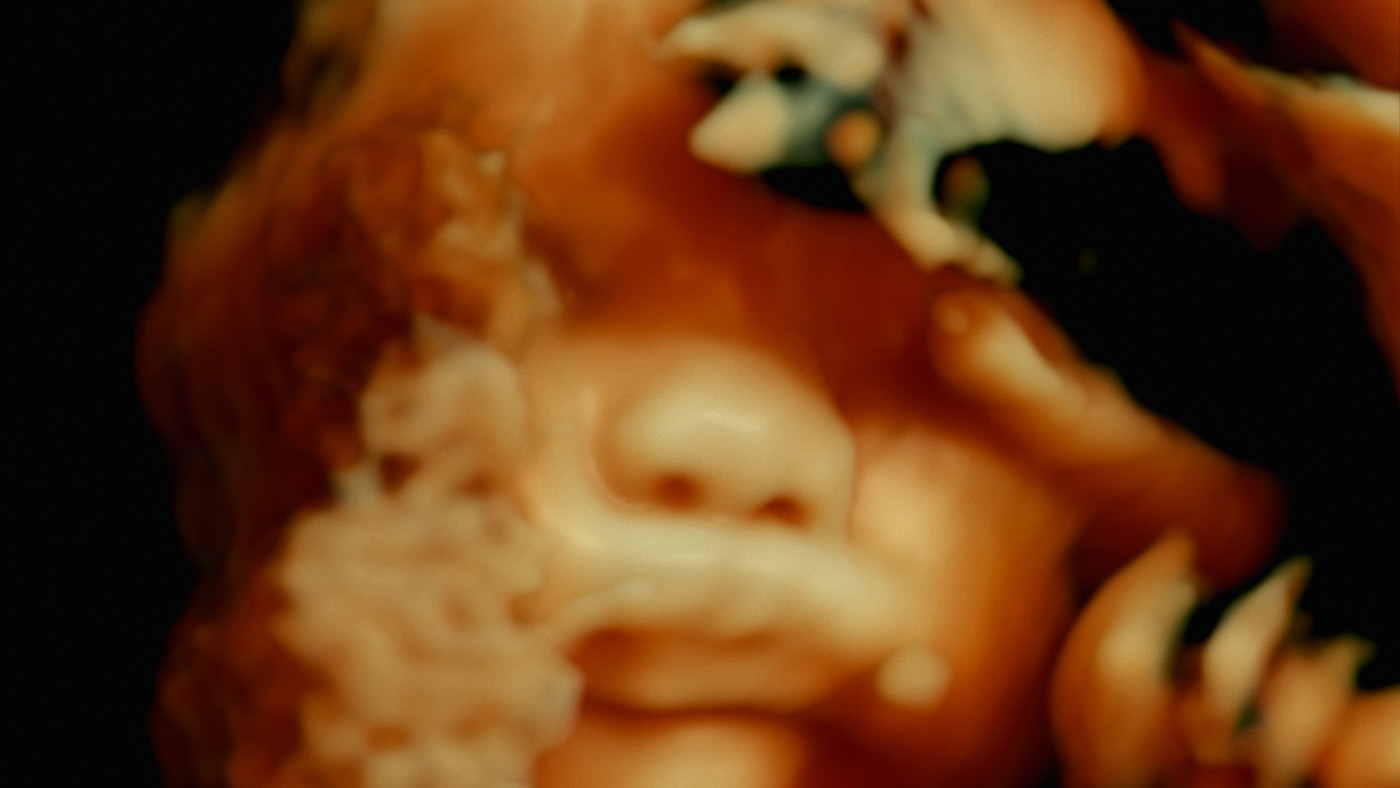

Jak by asi vypadal film, ohledávající lidské tělo nikoliv zvnějšku, nýbrž zevnitř? Na to odpovídá fascinující chirurgický trip s nečekaně artovou katarzí. Otrlým festivalovým matadorům přinese nesmírně silný fyzický zážitek. Před extrémním námětem a jeho neméně vyhraněným zpracováním však musíme výslovně varovat citlivé jedince.

Jak by asi vypadal film, ohledávající lidské tělo nikoliv zvnějšku, nýbrž zevnitř? Na odpověď si troufá dvojice antropologů z vyhlášené Laboratoře senzorické etnografie při Harvardu, jejichž tvorba pravidelně útočí na rozličná dokumentaristická tabu. Na fascinující cestě krajinou lidských tkání se brodí zdivočelým krevním řečištěm, obkrouží futuristicky tvarované orgány a na chvíli spočinou u majestátně vyhřezlé páteře. Chirurgický trip s nečekaně artovou katarzí přinese otrlým festivalovým matadorům nesmírně silný fyzický zážitek. Před extrémním námětem a jeho neméně vyhraněným zpracováním však musíme výslovně varovat citlivé jedince.